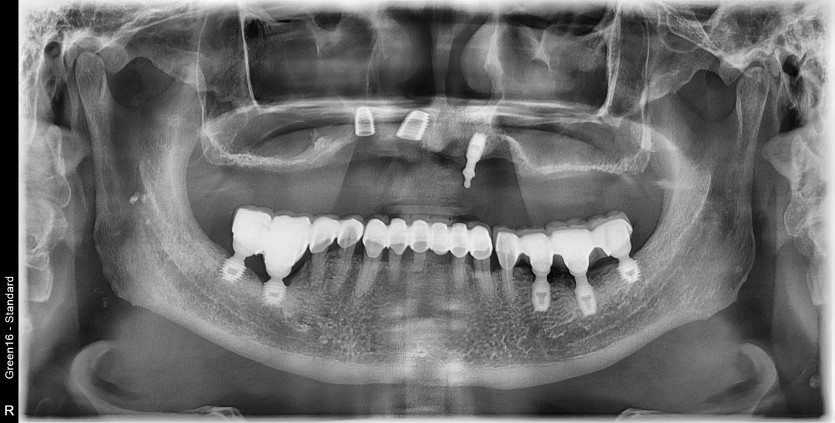

만 73세 상악 전체 임플란트 증례(기존 임플란트 제거)

상악 전체 임플란트 증례입니다.

9개의 임플란트로 완성하였습니다.